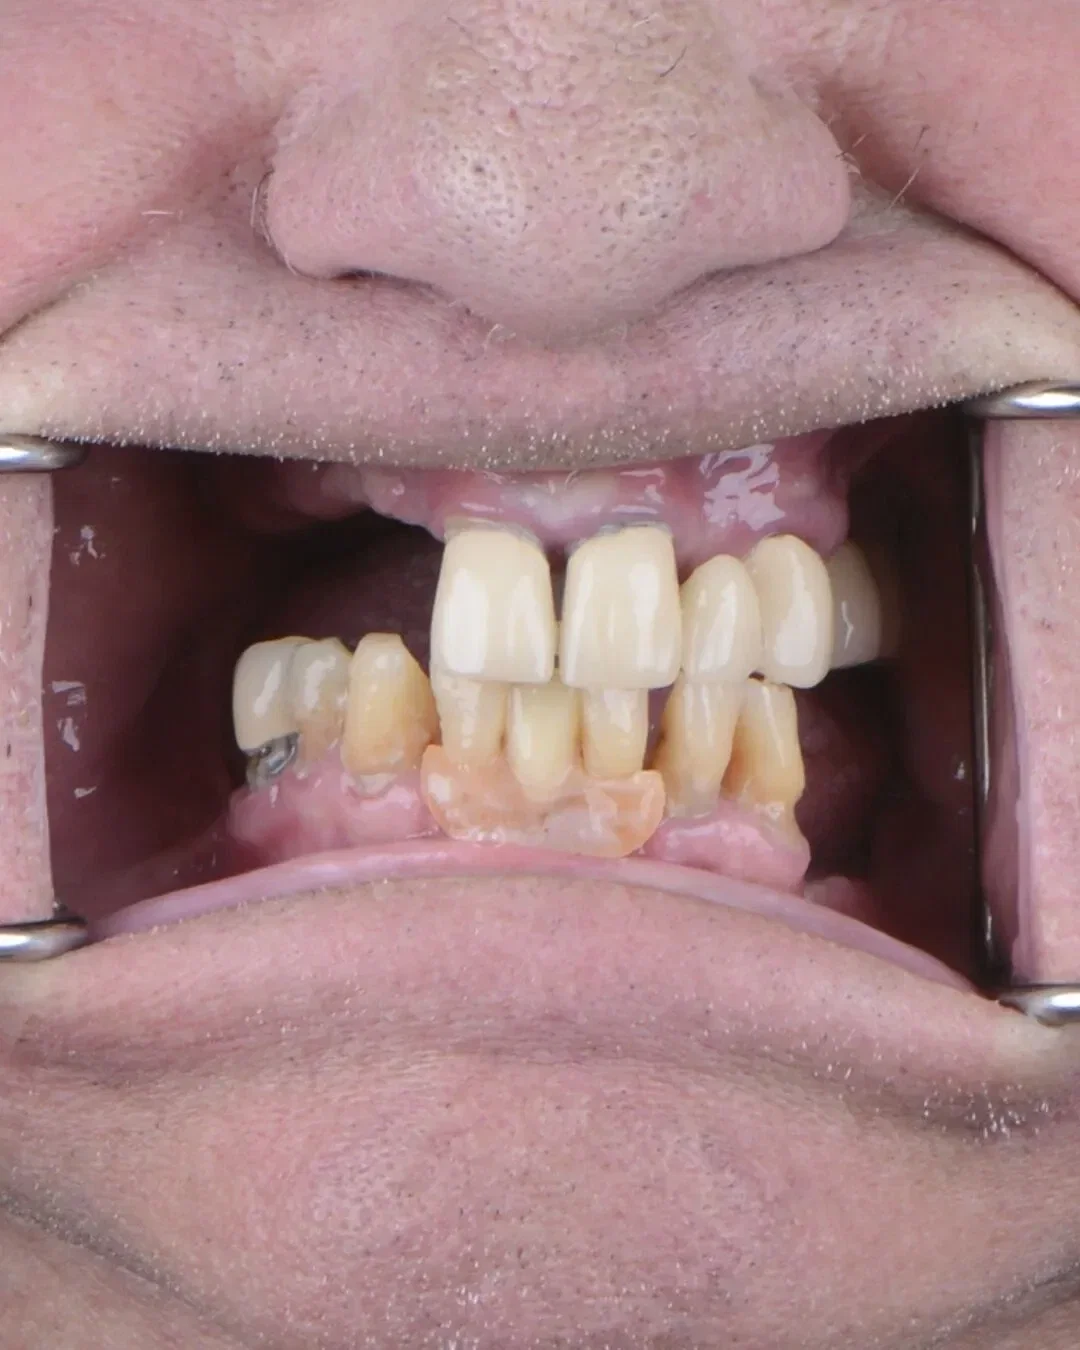

Real Smile Transformations

See the life-changing results from real patients who chose Fusion Dental Implants.

Your jawbone shrinks β losing density every month without a tooth root in place.

Surrounding teeth shift and loosen β creating new problems that need treatment.

More procedures pile up β bone grafts, extractions, and complex surgeries that weren't needed before.